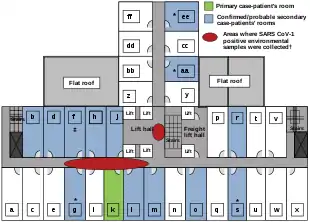

Another larger cluster of cases in Hong Kong centred on the Amoy Gardens housing estate. Its spread is suspected to have been facilitated by defects in its bathroom drainage system that allowed sewer gases including virus particles to vent into the room. Bathroom fans exhausted the gases and wind carried the contagion to adjacent downwind complexes. Concerned citizens in Hong Kong worried that information was not reaching people quickly enough and created a website called sosick.org, which eventually forced the Hong Kong government to provide information related to SARS in a timely manner.[51] The first cohort of affected people were discharged from hospital on 29 March 2003.[52]